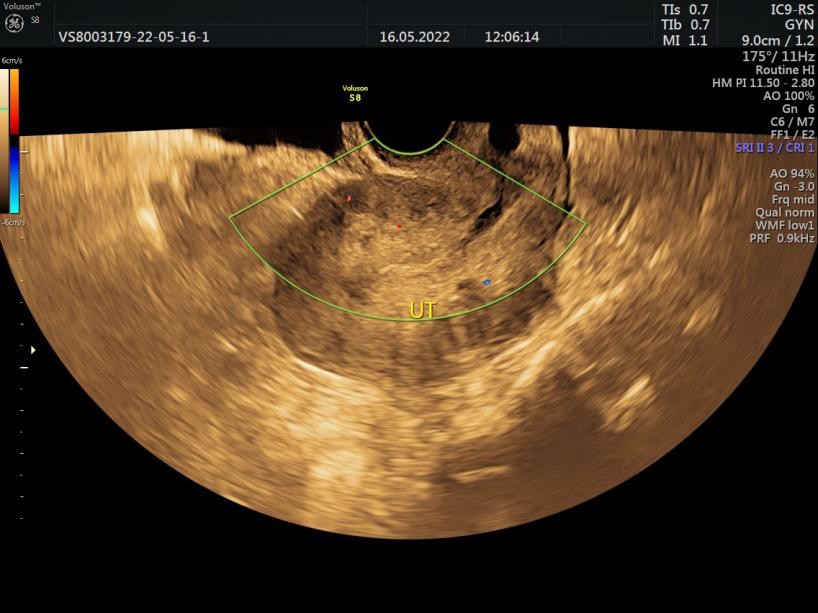

入院后,沈媛主任对方女士进行充分细致的病情评估,采用定位彩超查看宫腔病灶大小和血流情况,彩超明显可见宫腔组织残留,最薄处仅剩8mm,残留组织植入宫壁不但分界不清,血流丰富粗大。经过沈媛评估病情后,黄晨玲子医生认真耐心地为病人实施子宫超声聚焦治疗。

术后2日宫腔排出胎盘组织,2周后复查彩超仅见少量宫腔积液,1月后复查彩超宫腔未见残留组织,内膜厚5mm,居中,光整。

术后1月复查彩超